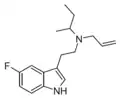

| MALT | artificial | H | CH3 | H2C=CH-CH2 | N-methyl-N-allyltryptamine | 1366416-29-6 |

| DALT | artificial | H | H2C=CH-CH2 | H2C=CH-CH2 | N,N-diallyltryptamine | 60676-77-9 |

| 5-Fluoro-sBALT | artificial | 5-F | CH(CH3)CH2CH3 | CH2CH=CH2 | 5-fluoro-N-sec-butyl-N-allyltryptamine | |